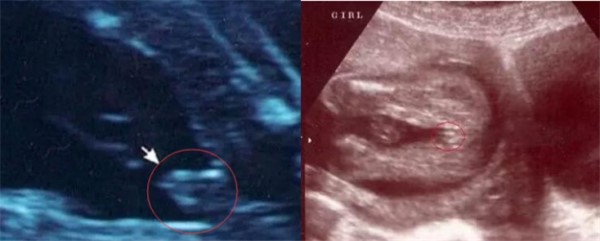

在给各位孕妈分享一个小知识,那就是男宝女宝四维彩超的显示图也会有不一样的地方:

1.怀的是男宝:如果四维的时候宝宝有凸出来的东西,这就是男孩的标志,也就是男宝宝的小jj,如果下面还有圆圆的那就是宝宝的蛋蛋,如果圆圆的还加一个小肠,那就是宝宝全部的jj了。

2.怀的是女宝:怀女孩的话照样也很明显,就比如三条白线是明显的女宝宝特征,如果没有三条白线的话,就看两腿之间有没有突突的东西,而且中间还有一个小凹槽,那这就是女宝宝无疑了。